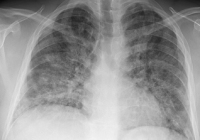

Thoraxröntgen

Abbildung 3: Thoraxröntgen

Keywords: Thoraxröntgen